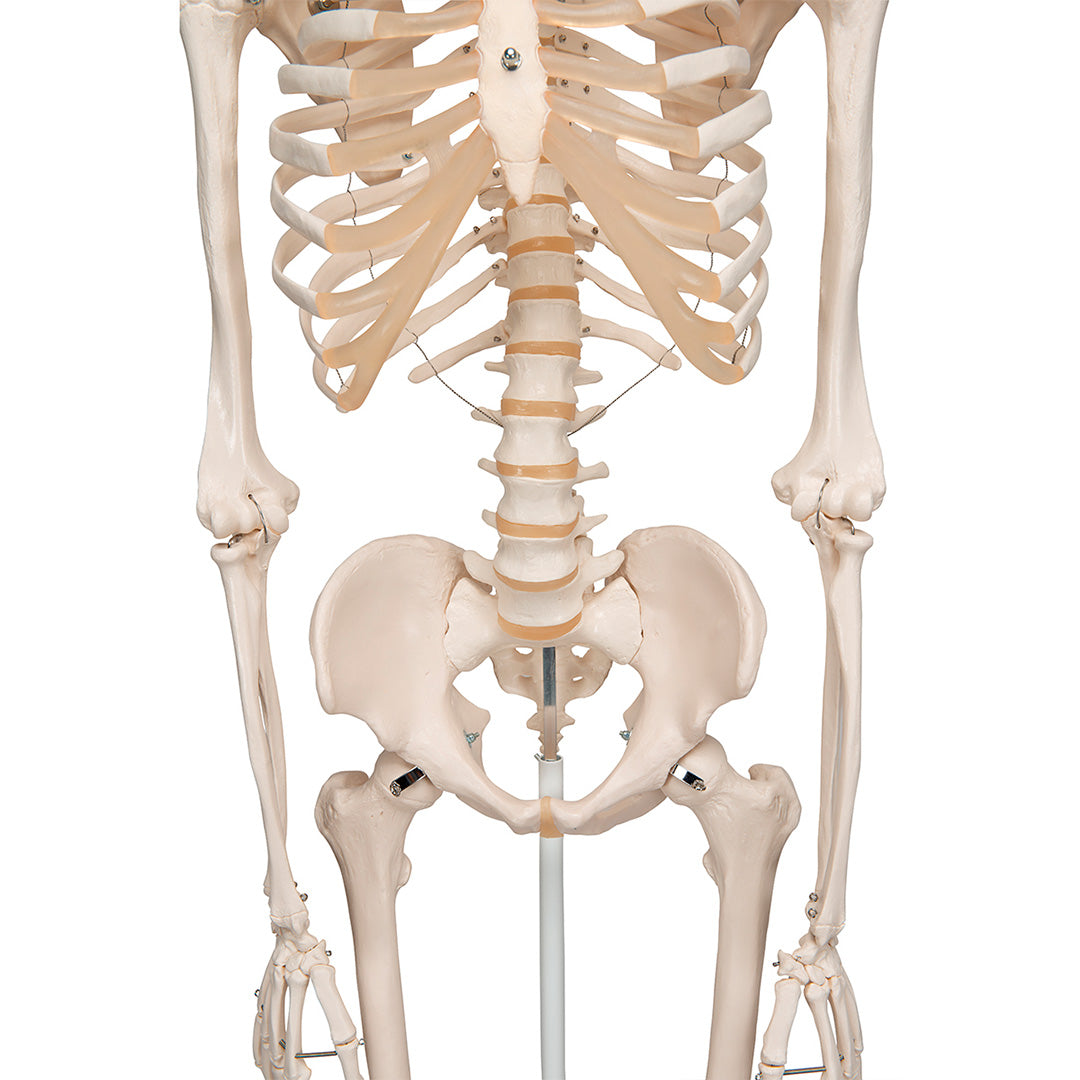

Calidad demostrada, postura aún más firme.

Stan, el modelo básico de esqueleto humano, es apreciado desde hace décadas en el mundo entero. Gracias a su excelente calidad y resistencia, es ideal para su uso en hospitales, colegios, universidades y laboratorios.

Decídase por un genuino Stan, el esqueleto artificial original

Características

Peso: 9.536 kg

Dimensión: 176.5 cm